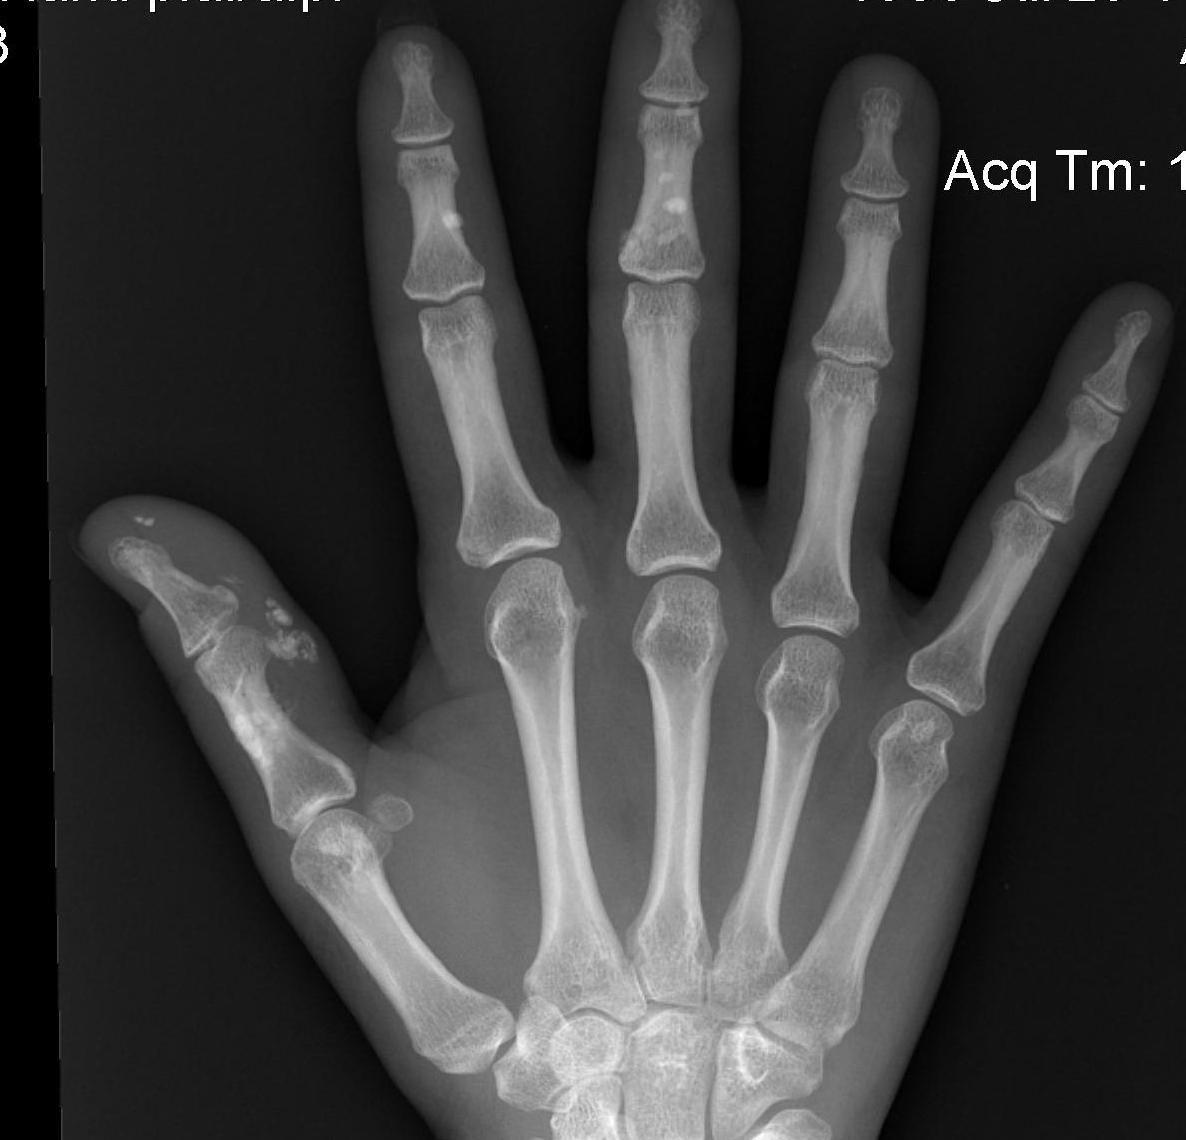

SLE

Pathology

Similar hand appearances to RA

- no joint destruction even in setting gross deformity

Xray

Effusions

Juxtacortical osteopenia

Subluxation / dislocation

Bone infarction and abnormal calcification

Joint destruction = Co-existent RA